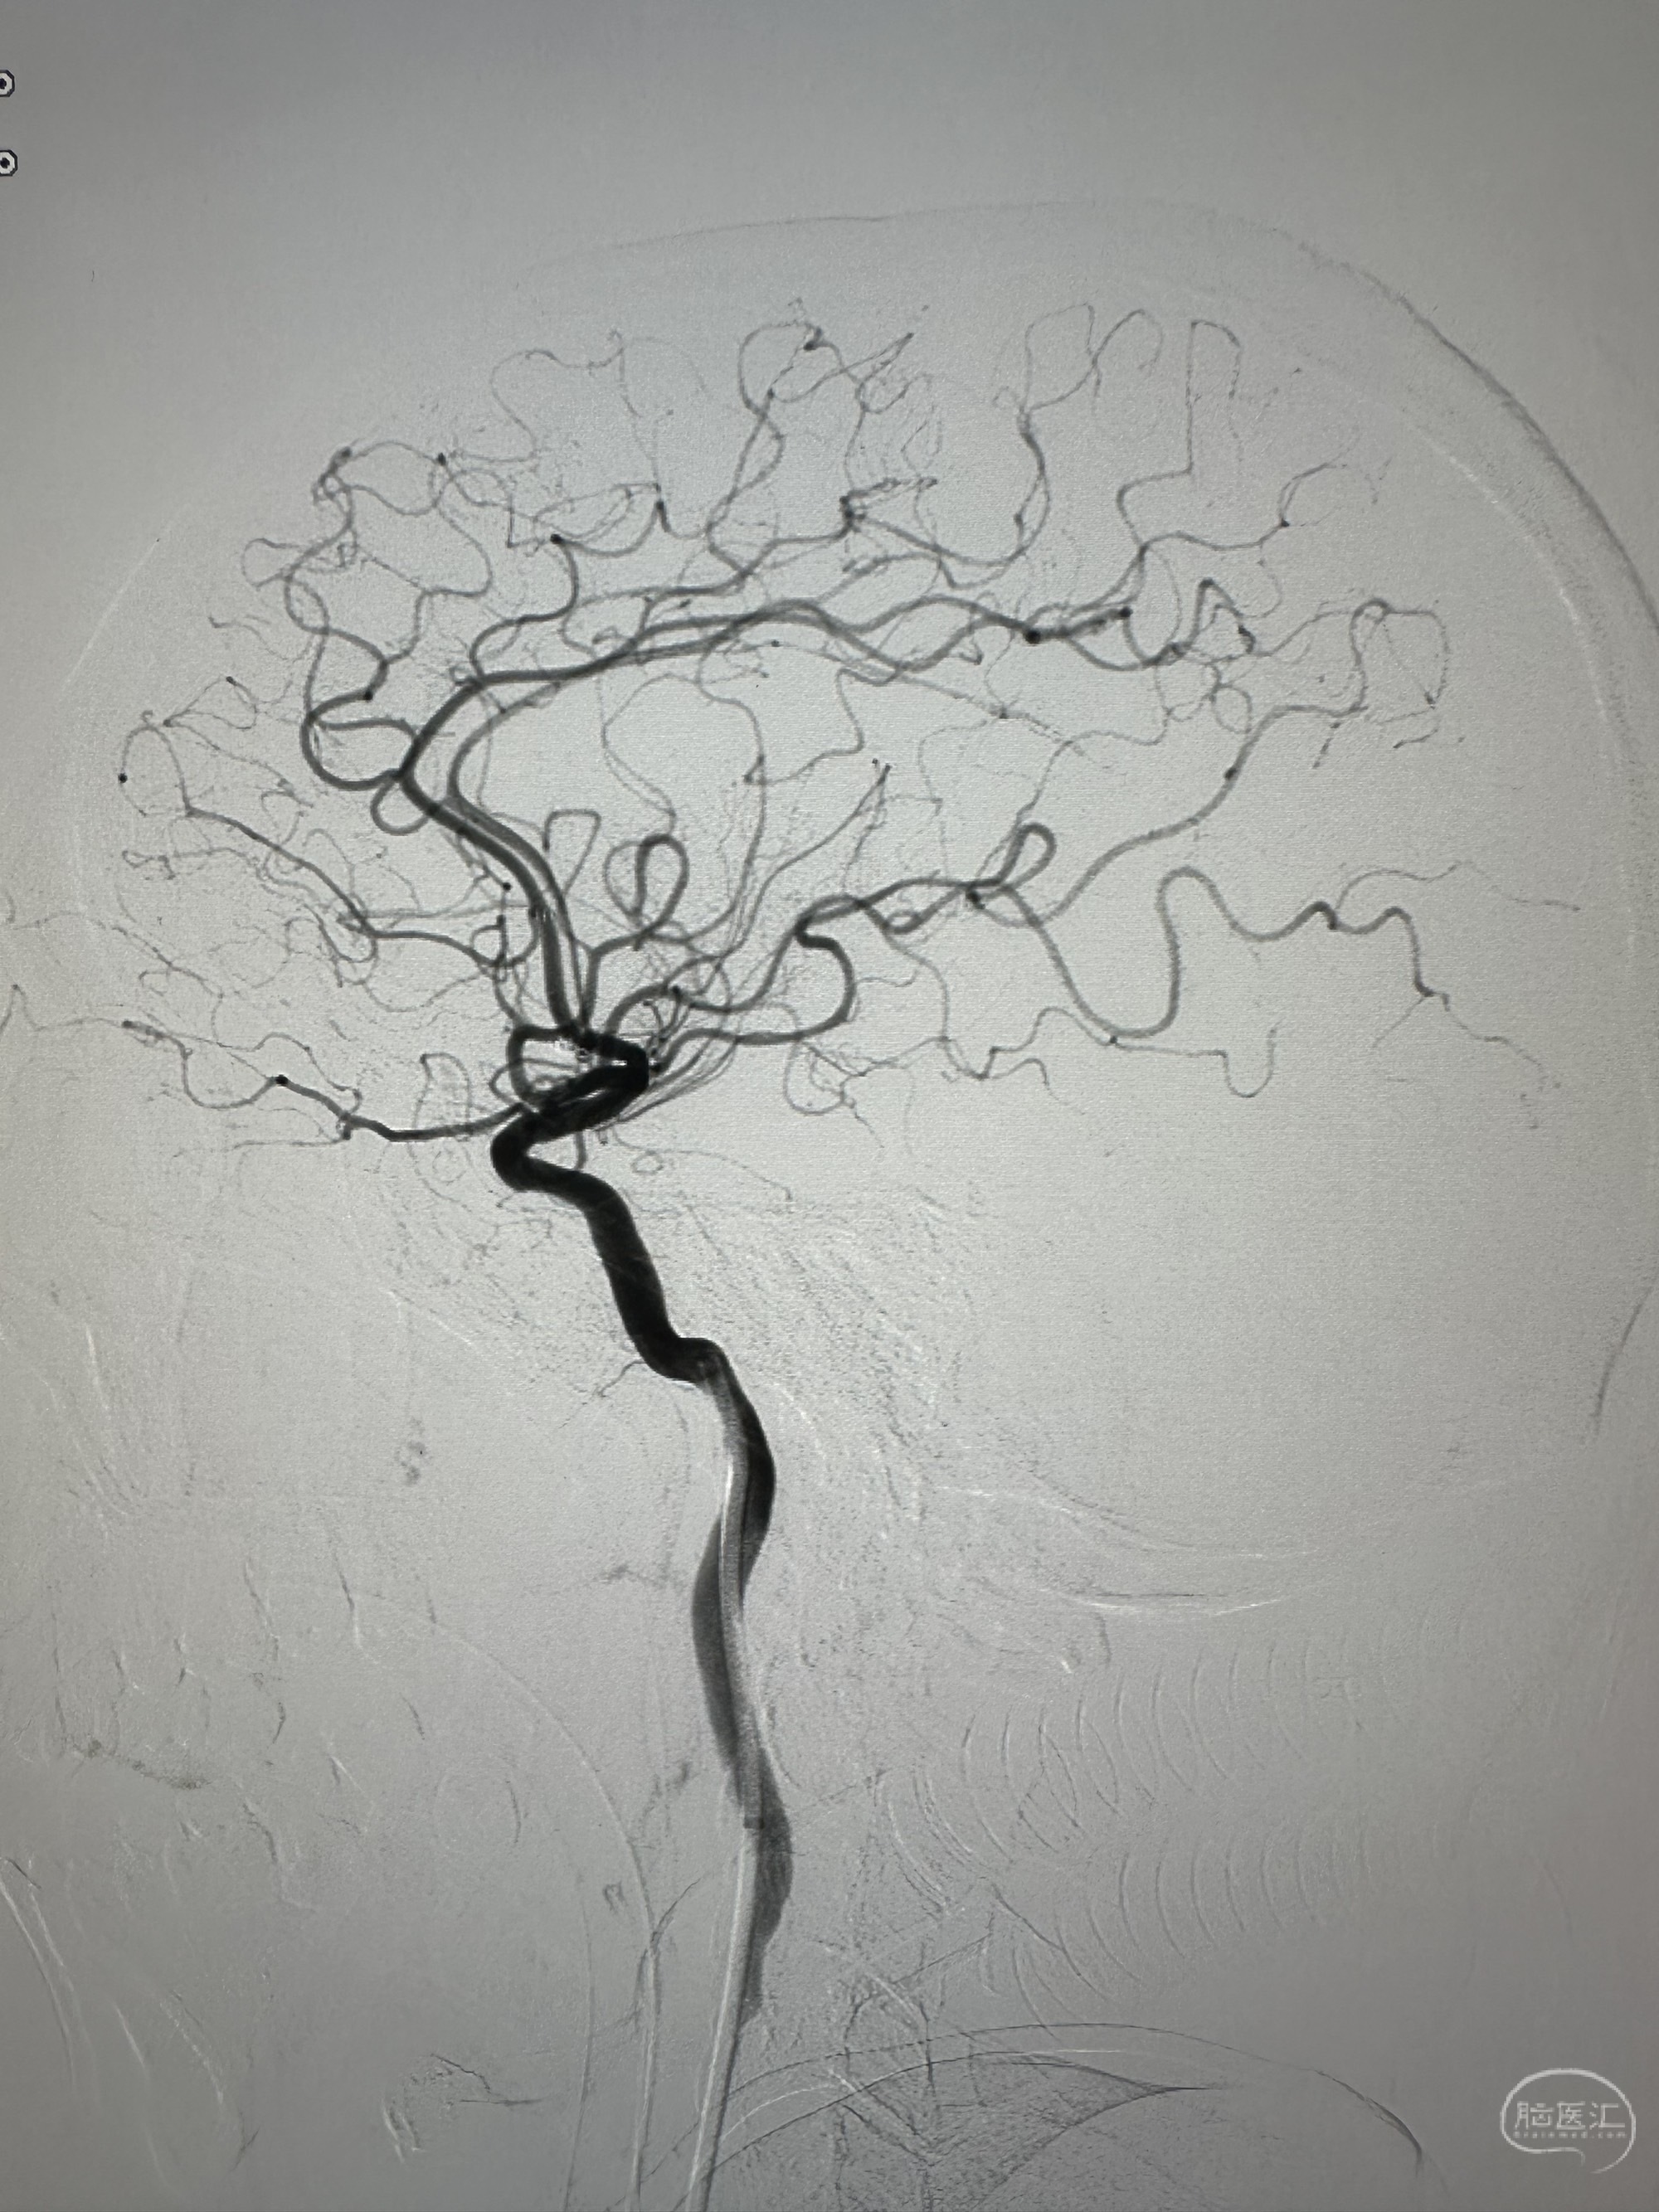

侧位

侧位